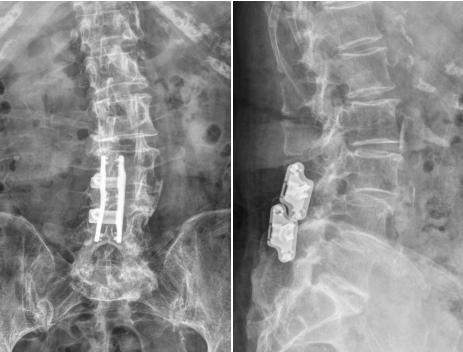

传统手术需行腰椎后路椎管减压椎间植骨融合内固定术,肌肉剥离广泛,且因需置入多枚椎弓根螺钉和椎间融合器达到完全固定融合效果,但是手术时间长出血多,术后存在邻近节段退变风险。而腰椎后路椎板部分切除减压棘突间内固定装置置入术仅需部分切除椎板进行减压,并植入棘突间固定装置,无需传统术式中较多的内置入物,能够降低手术创伤,患者痛苦相对小,术后恢复快。

▲术后侧弯亦得到纠正

手术当日,脊柱外科(骨四科)团队为患者施行手术。术中团队操作精细,全程密切配合,仅1小时30分钟手术顺利结束。术后患者恢复良好,腰腿痛明显好转。术后三天患者即可下地行走,术前存在的下肢疼痛、麻木及双腿沉重感均得到明显改善。